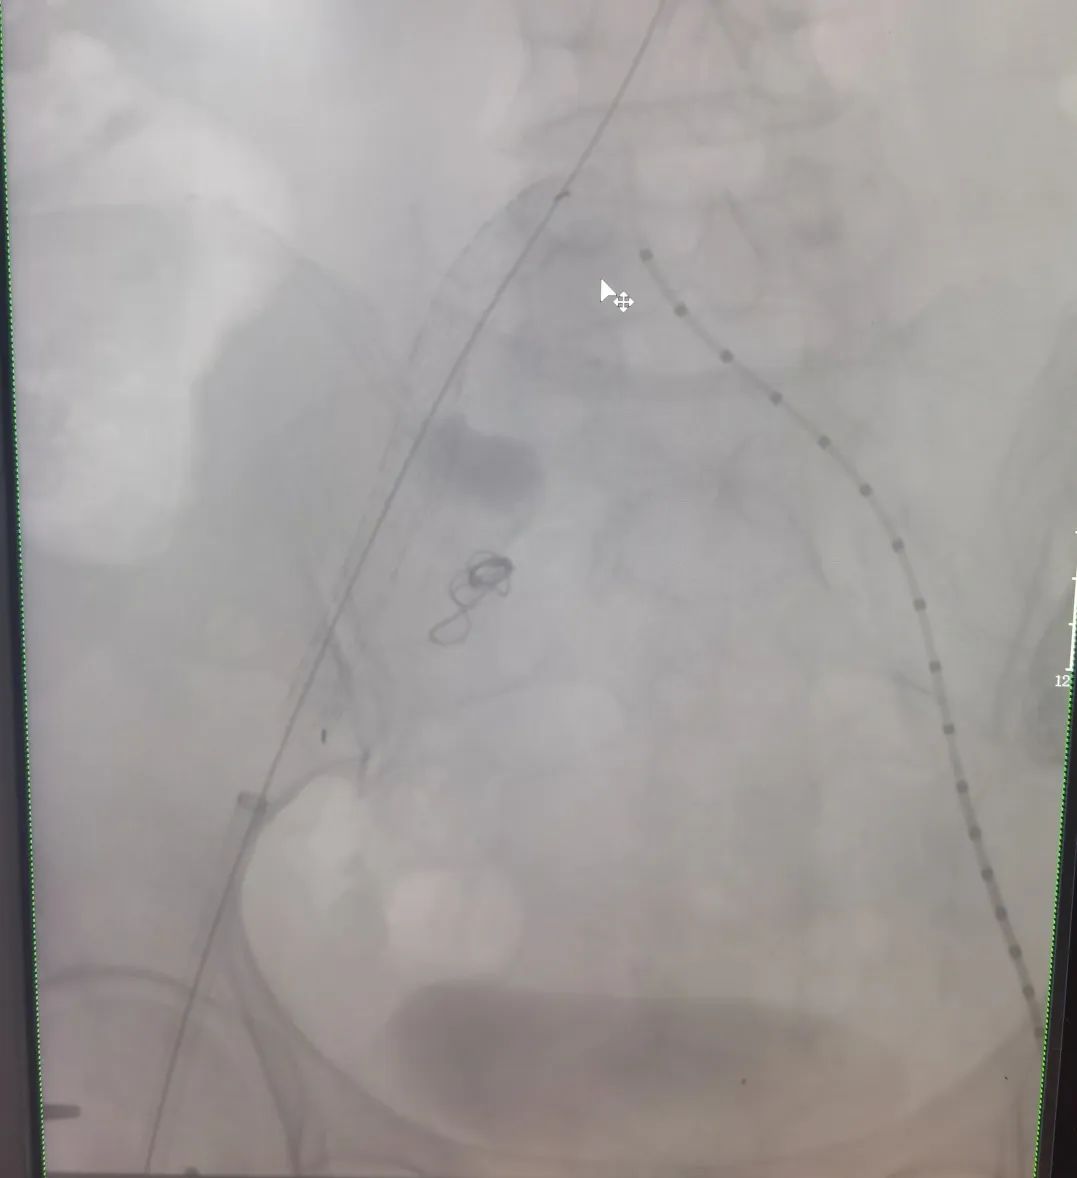

▲术后图

在麻醉科卜美林主任的守护下,桂锐主任协同胡玉东主任和血管外科团队,准确定位目标血管,顺利置入支架,隔绝瘤体,将陈奶奶从死亡威胁中解救出来。在广济医院外科团队精准高效地治疗下,陈奶奶很快康复出院。